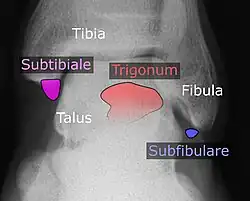

Ankle

Accessory bones at the ankle mainly include:

- Os subtibiale, with a prevalence of approximately 1%.[14] It is a secondary ossification center of the distal tibia that appears during the first year of life, and which in most people fuses with the shaft at approximately 15 years in females and approximately 17 years in males.[14]

- Os subfibulare, with a prevalence of approximately 0.2%.[15]

Os trigonum (further described below) may also be seen on an ankle X-ray.

Os trigonum

The os trigonum or accessory talus represents a failure of fusion of the lateral tubercle of the posterior process of the talus bone. Is estimated to be present in 7–25% of adults.[17] It can be mistaken for an avulsion fracture of lateral tubercle of talus (Shepherd fracture) or a fracture of the Stieda process. In most cases, Os Trigonum will go unnoticed, but with some ankle injuries it can get trapped between the heel and ankle bones which irritates the surrounding structures, leading to Os Trigonum Syndrome.[21]